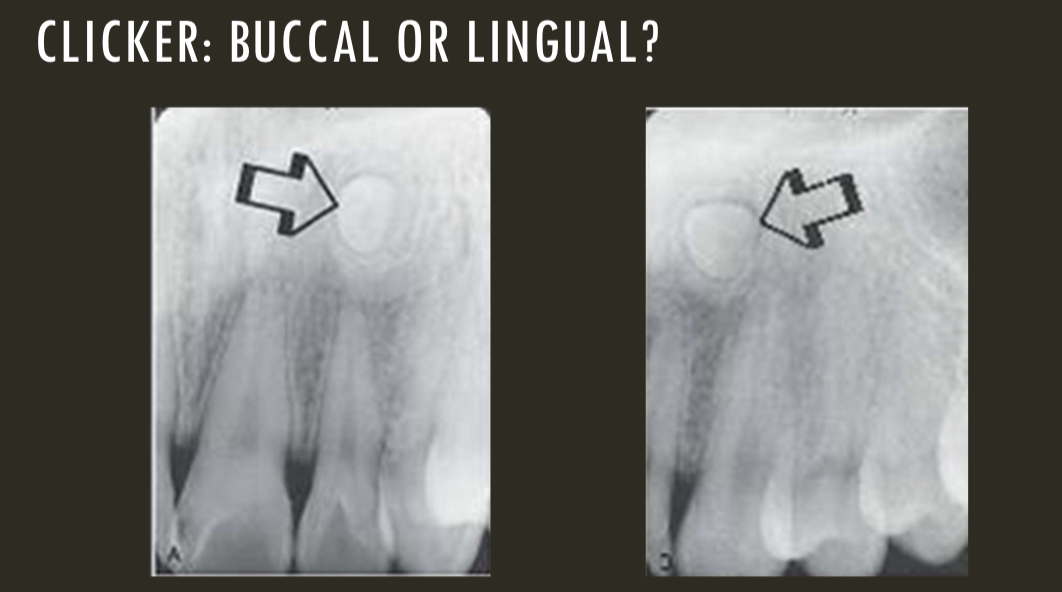

buccal object rule

expose 1st image (PA or bw)

take a second image with a different H or V angulation aka same area different angle

compare images to see how the object shifted in the image

SLOB

lingual

right angle technique

buccal

lingual

lingual

buccal